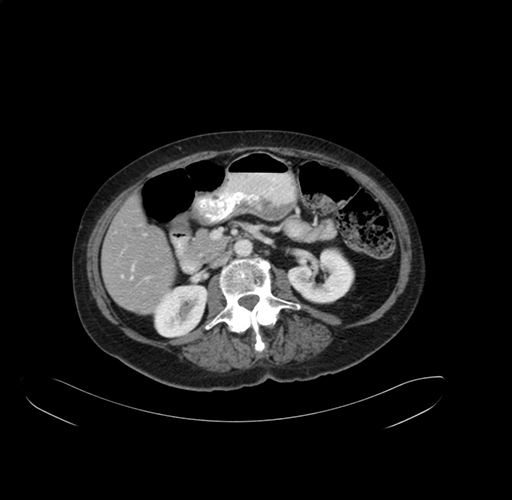

Axial Venous